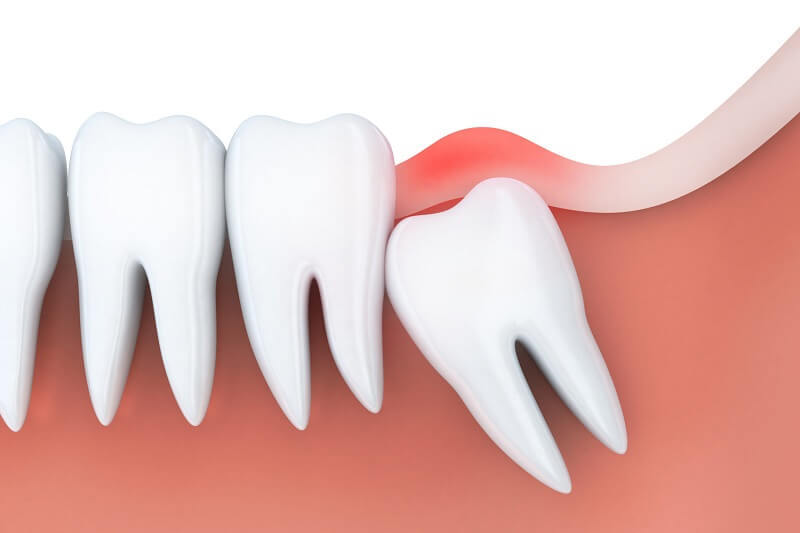

Ảnh hưởng mô mềm xung quanh: Thức ăn đọng bám xung quanh răng khôn cũng gây ra tình trạng sưng, đỏ và đau vùng nướu quanh răng khôn, gọi là viêm quanh thân răng (viêm lợi trùm). Đối với răng khôn hàm trên lệch ngoài hoặc trồi, khi ăn nhai sẽ gây ra tình trạng chấn thương mô má hoặc mô nướu hàm dưới.

Bệnh nha chu: Việc khó vệ sinh chải rửa vùng răng khôn còn dẫn đến bệnh lý nha chu ở vùng này, lâu dài sẽ gây tiêu xương quanh răng và răng kế cận nó.